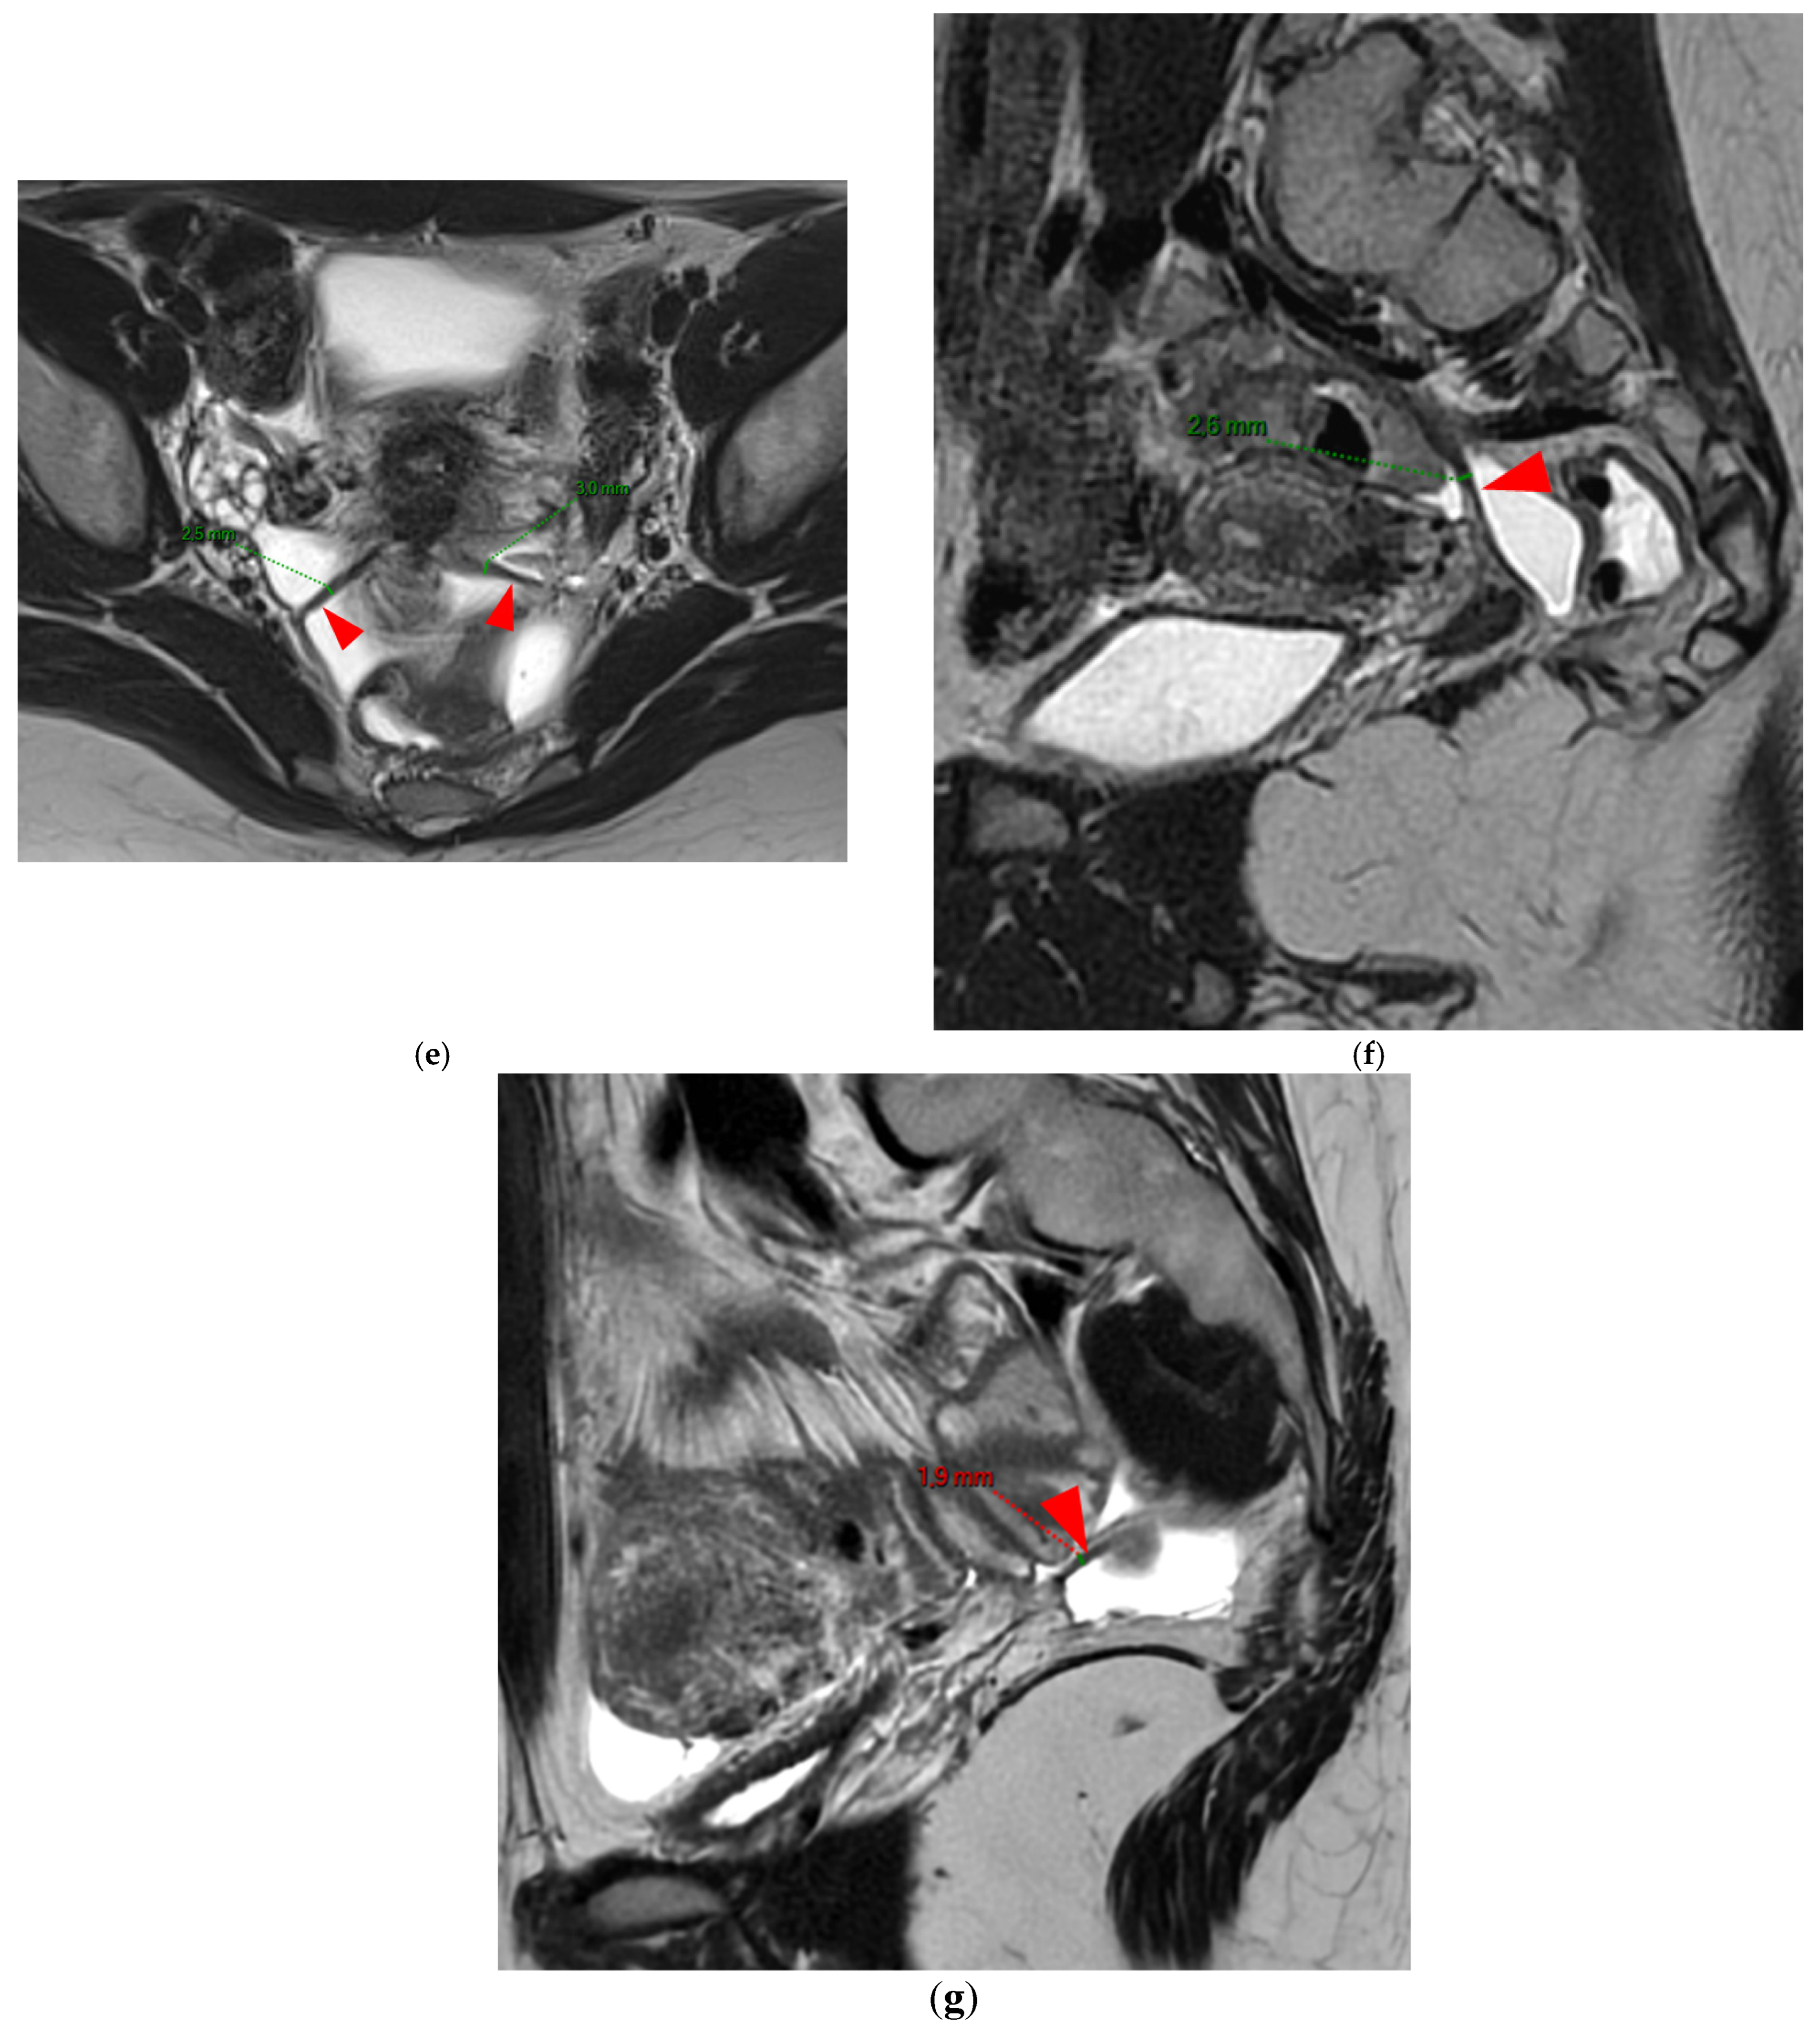

Figure 4. Pelvic MRI scans of seven patients with HTD type 3B USLs. (a) Sagittal T2WI: a thickened (2.1 mm) and stiffened right USL (arrowhead) with “bowstringing”. (b) Axial T2WI: a caliber disparity (dashed arrows) with focal thickening (4.2 mm) of the left proximal USL (arrowhead). (c) Sagittal T2WI: a caliber disparity (dashed arrows) with focal thickening (2.5 mm) of the right distal USL. (d) Axial T2WI: a right USL with a notched and irregular surface (dashed arrows). (e) Axial T2WI: thickened and stiffened left (3 mm) and right (2.5 mm) USLs with “bowstringing” of both USLs (arrowheads). (f) Sagittal T2WI: a thickened (2.6 mm) right USL with a stiffened appearance characterized by a steep vertical orientation (arrowhead). (g) Sagittal T2WI: the right USL appears thin (1.9 mm) but stiffened (arrowhead), exhibiting “bowstringing”. These findings led to its reclassification from type 2 to type 3B.